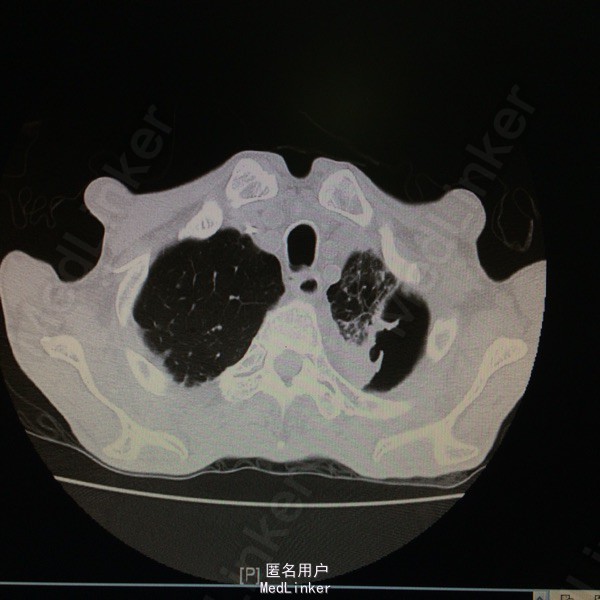

查体:T37.7度,P130次/分,BP 77/59次/分,神情,恶病质,双肺呼吸音粗,未及干湿罗音。 辅助检查:胸部CT示:双肺感染、左肺实变部分坏死。支气管镜示:左上叶气管黏膜感染:真菌?结核?黏膜病理报:符合真菌感染,形态学考虑为曲菌。多次痰培养示:曲霉菌感染。白细胞 12.9*10E9/L,CRP 140ng/ml,ESR 140mm/h,PCT 0.676ng/ml。

随访:患者现予“伏立康唑、两性B”治疗,体温正常,咳嗽咳痰明显好转。复查胸部CT示:左肺上叶病变较前进展,下叶病变较前吸收,左肺实变部分坏死空洞范围较前扩大。 讨论:据痰培养及病理,可明确诊断“肺曲霉菌感染”;予两性霉素B治疗后体温可降至正常,支持该患者发热为曲霉菌感染所致。痰培养及病理结果均支持曲霉菌感染的病例还是少见的。就患者体温变化而言,示治疗有效;其胸部CT示左肺坏死空洞较前扩大,其左肺大部分为坏死组织,空洞会随着这些组织的排出而变大。